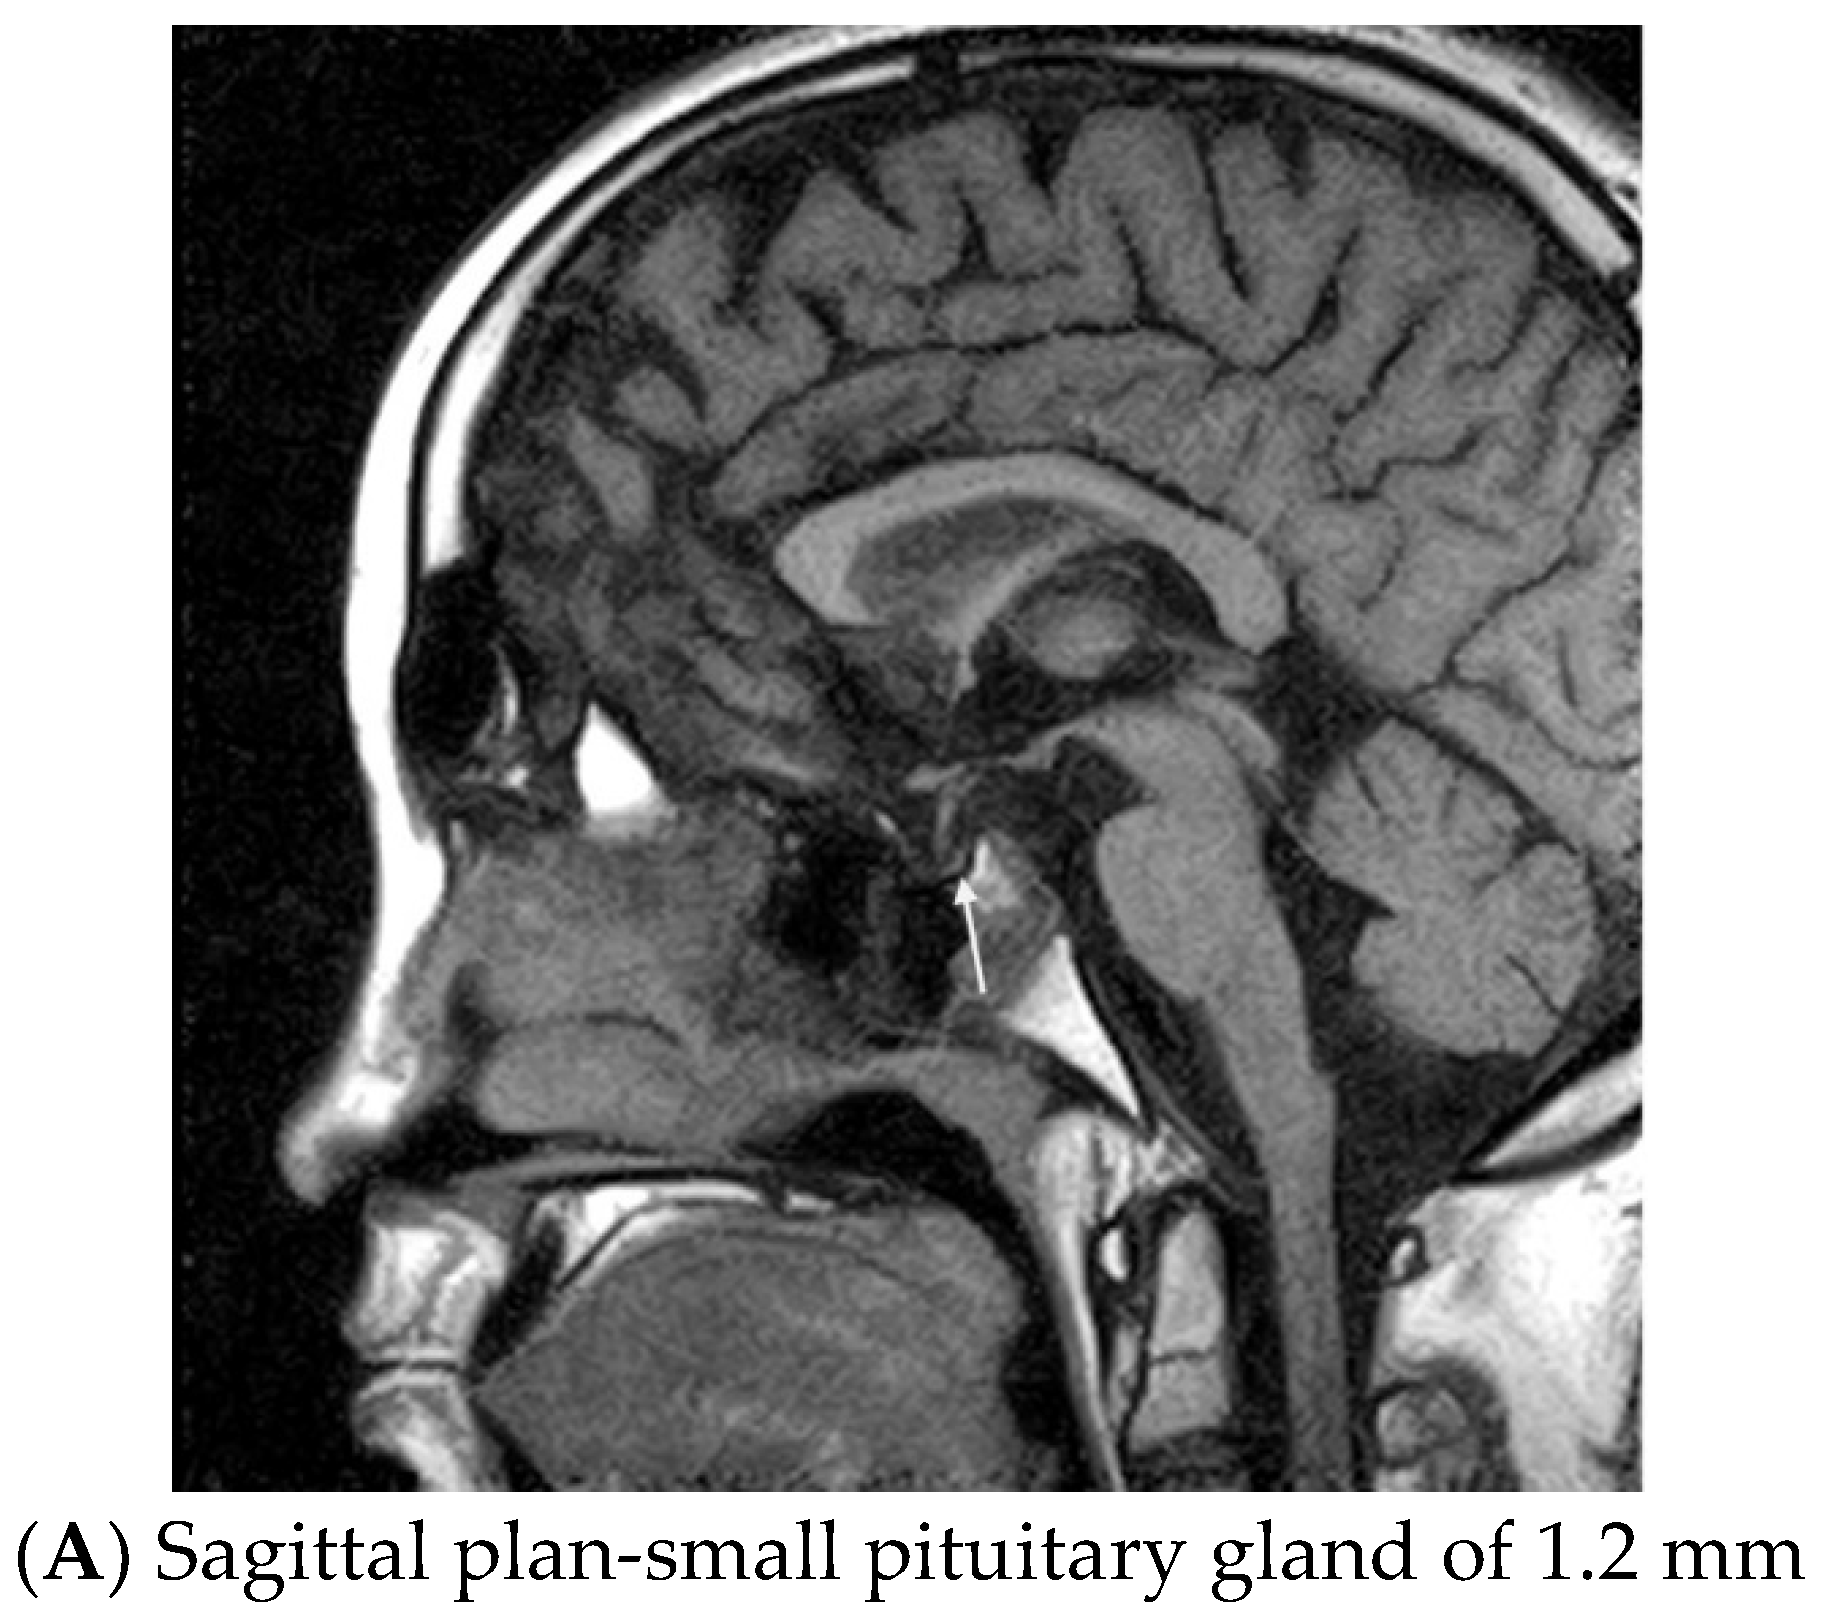

- Schneider, H.J.; Sämann, P.G.; Schneider, M.; Croce, C.G.; Corneli, G.; Sievers, C.; Ghigo, E.; Stalla, G.K.; Aimaretti, G. Pi-tuitary imaging abnormalities in patients with and without hypopituitarism after traumatic brain injury. J. Endocrinol. Invest. 2007, 30, RC9–RC12. [Google Scholar] [CrossRef]